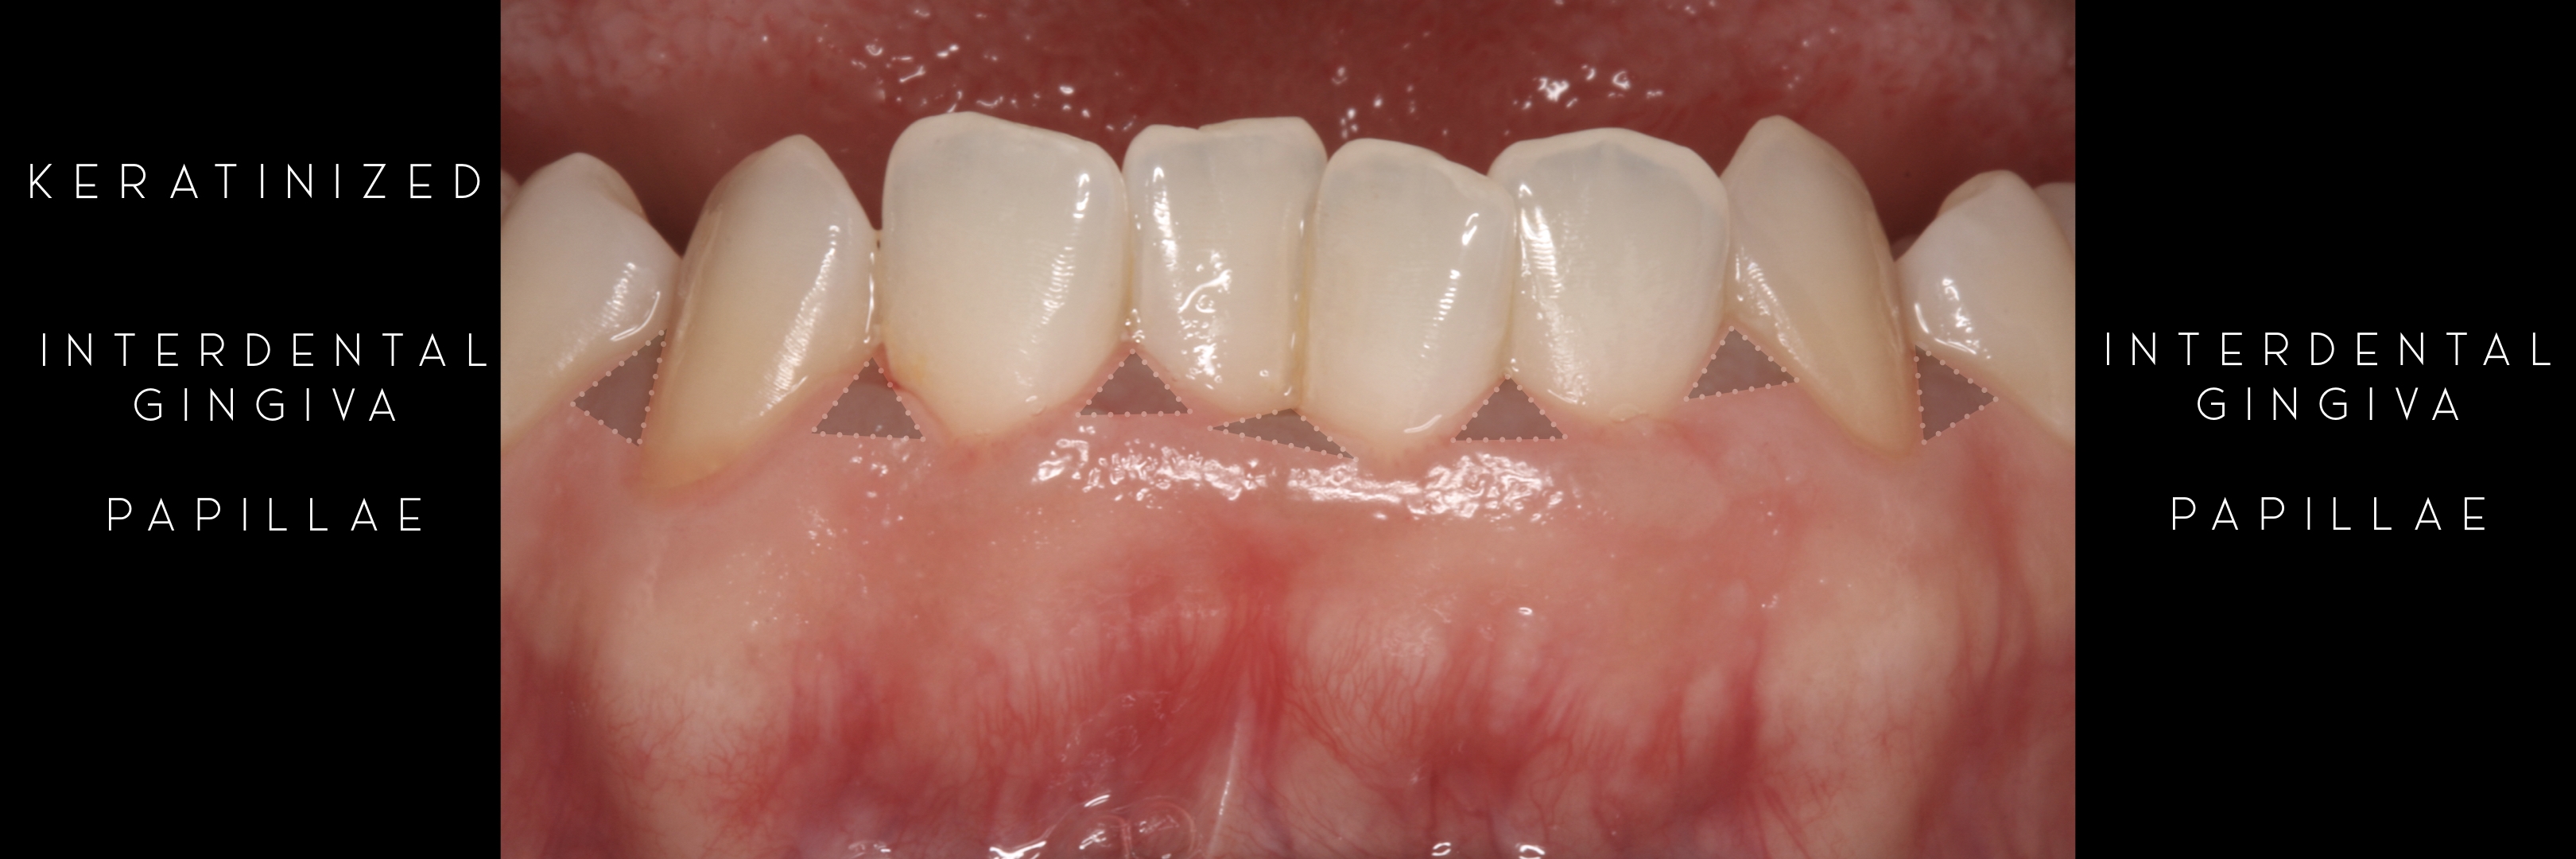

KERATINIZED gingiva includes

the free gingiva

(marginal gingiva & papillae)

and the attached gingiva extending from the gingival mar­gin to the mucogingival junction.

Generally we tend to forget about these 2 parameters, free and the attached gingiva are both essential parts of the keratinized gingiva.

This meaning that keratinized (load bearing capacity) is a mechanical characteristic that makes up for attached gingiva, providing it's immobility,  but also is of such importance as the thickness it provides around whatever perforates the epithelium, be it implants or teeth, being also keratinized (having load bearing capacity) at this location.